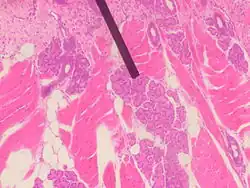

Von Ebner's gland

Human Von Ebner's gland

Von Ebner's glands, also called Ebner's glands or gustatory glands, are exocrine glands found in the mouth. More specifically, they are serous salivary glands which reside adjacent to the moats surrounding the circumvallate and foliate papillae just anterior to the posterior third of the tongue in its submucosa, anterior to the terminal sulcus.